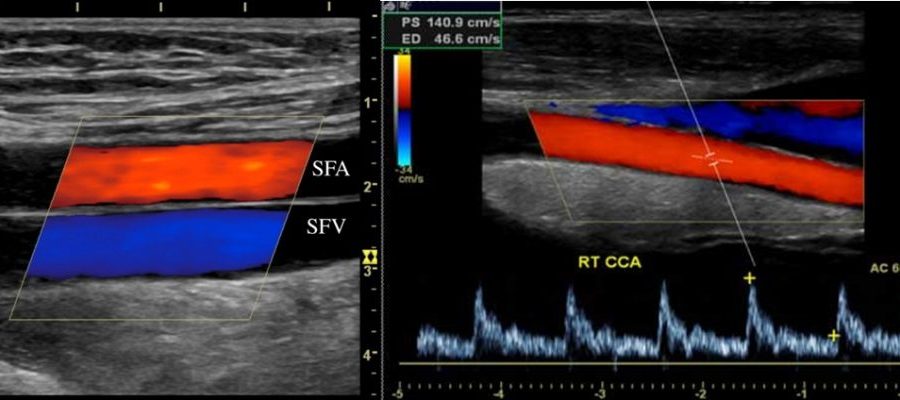

Thanks to the imaging processes performed, physiological and anatomical information about the vessels and images related to blood flow are obtained.

It also provides the opportunity to examine blood flow velocities and blood flow in the lower artery Doppler arteries, which are requested from people with suspected circulatory disorders. For this reason, arterial Doppler is requested from the patients in the lower extremities to investigate whether there is a critical condition in the artery.

In addition, the presence of plaque on the vessel walls can be detected by color Doppler. Lower extremity artery Doppler imaging is usually requested from people with suspected stenosis or occlusion of their arteries.